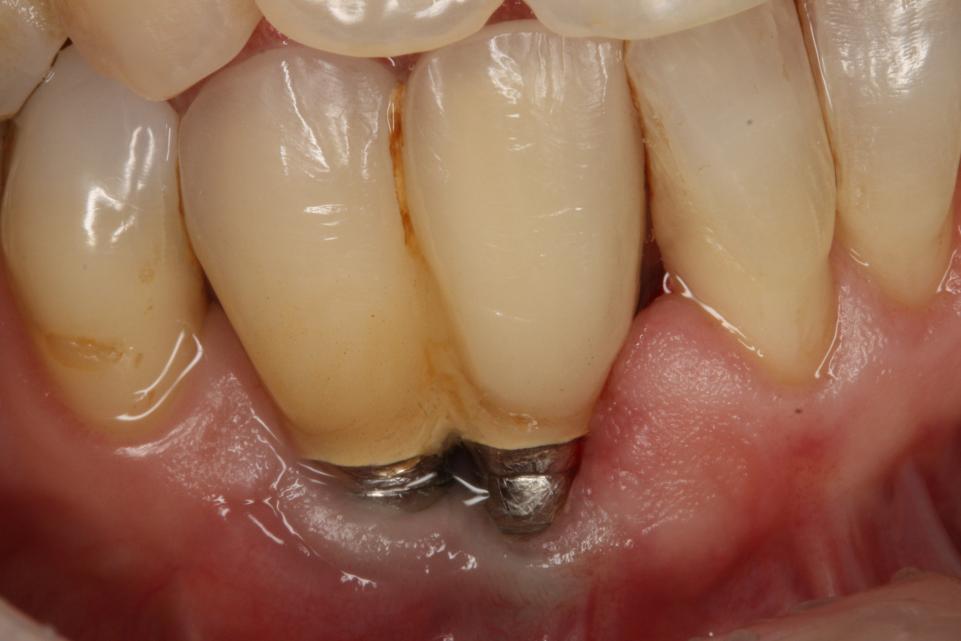

Também é uma lesão inflamatória causada pela ação da placa bacteriana em sulco peri-implantar, no entanto, essa lesão avança para os ossos de suporte, podendo levar à perda da união funcional entre osso e implante.

É como se fosse um segundo estágio da mucosite, trazendo mais sintomas como vermelhidão gengival, inchaço, presença de edemas, formação de pus, sangramentos, perda óssea e até mesmo a mobilidade.

É possível que, nesse estágio, haja perda progressiva e significativa do osso onde o implante foi realizado.